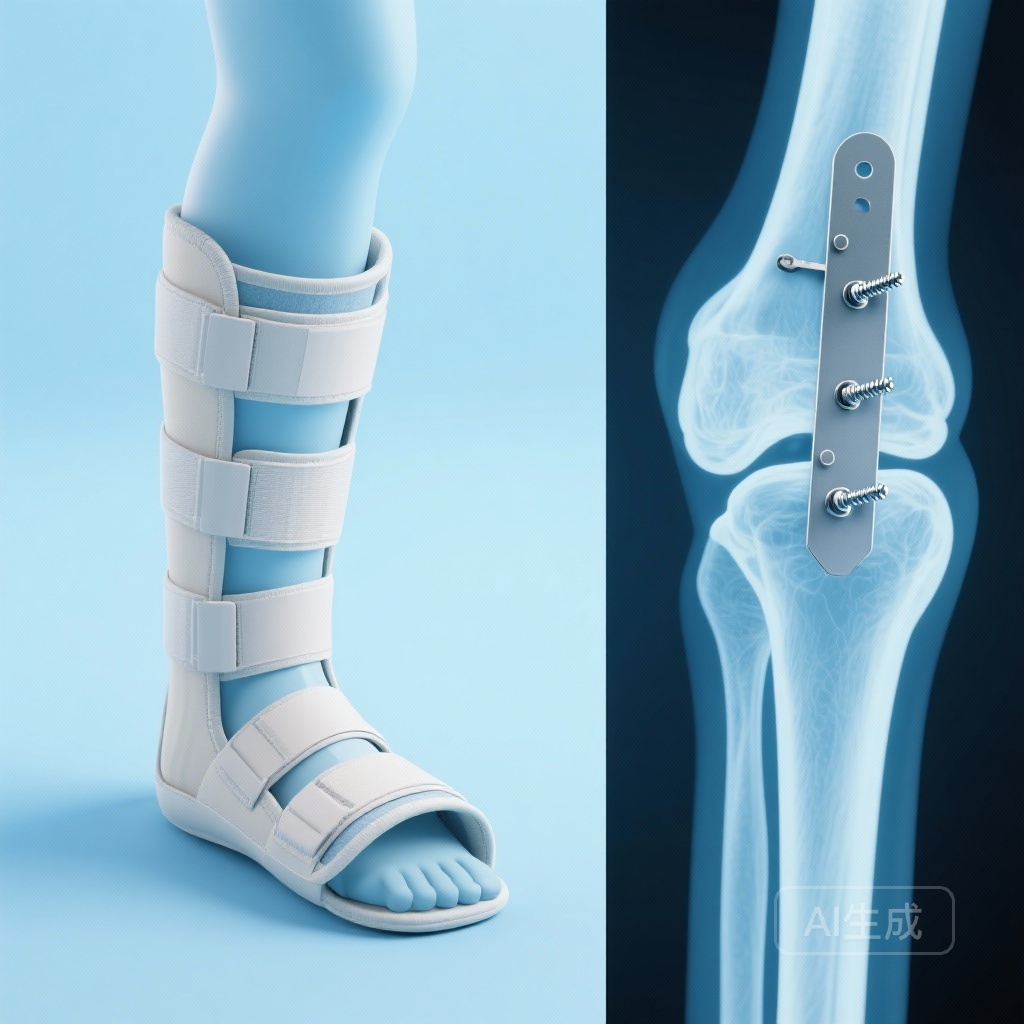

外側骨端骨折、特にDanis-Weber Type Bに分類されるものは、整形外科医が管理する最も一般的な損傷の一つです。静的なレントゲン画像で明らかな移位やモルテーズ拡大がある骨折は、手術が必要とされていますが、重要な「グレーゾーン」が存在します。それは、初期の静的X線画像では一致しているが、外部回転ストレステストで不安定性(具体的には距骨のシフト)が確認される単一骨端のウェーバーB型骨折です。

SUPER-FIN試験は、2013年から2021年にかけてフィンランドの専門大学病院の外傷センターで行われた実践的な無作為化非劣性臨床試験です。対象は骨格が成熟した患者(16歳以上)で、孤立したウェーバーB型腓骨骨折を呈していた者でした。参加基準は厳格で、患者は静的なレントゲン画像で足首のモルテーズが一致しているが、フッ素造影下で標準化された外部回転ストレステストで不安定性が確認されていることが必要でした。

1. ギプス固定群 (n=62)

参加者は6週間の通常の膝下ギプスを受けました。体重負荷プロトコルは、実践的な臨床実践を反映するために研究全体で標準化されました。

2. 手術群 (n=64)

参加者は開放還元内固定(ORIF)を受け、その後、保存群と同じ6週間のギプス固定プロトコルが行われました。